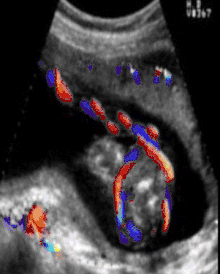

A study published in 2004 was done to establish the sensitivity of ultrasound in the diagnosis of a nuchal cord. Each of 289 women, induced the same day, underwent a transabdominal ultrasound scan with an Aloka 1700 ultrasound machine with a 3.5 MHz abdominal probe, using gray-scale and color Doppler imaging immediately prior to induction of labor. Presence of the cord was sought in the transverse and sagittal plane of the neck. A nuchal cord was diagnosed if the cord was visualized lying around at least 3 of the 4 sides of the neck. A cord was actually present at delivery in 52 of the 289 women. Only 18 of the 52 cords or 35% of the nuchal cords were detected on ultrasound done immediately before delivery, and 65% of nuchal cords were not detected. Of the 237 cases where there was no cord at delivery, ultrasound had false positive results, i.e. diagnosed a cord in 44 of the 237 cases (19%) in which there was no cord present at all. In this study, ultrasound was only 35% accurate at finding a single loop, and only 60% accurate at detecting a nuchal cord wrapped multiple times around the neck.[9]